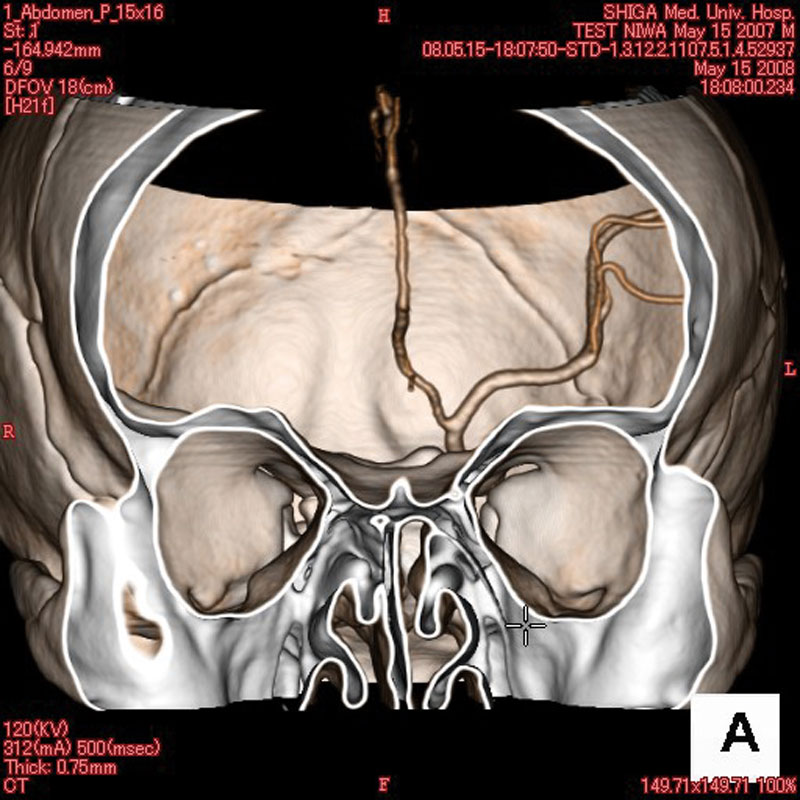

- Dieses Modell besteht aus einem synthetischen Schädel, welcher in einen Kunststoffkopf eingegossen ist.

- In der linken Schädelhälfte sind die vordere und mittlere Hirnarterie nachgebildet und mit Kontrastmittel gefüllt.

- Der Durchmesser der simulierten Arterien reicht von 0,5 mm bis 4 mm.